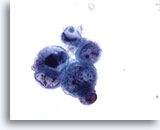

Figure 33

Catheterized urine, high grade urothelial carcinoma

Nuclei of high grade urothelial carcinoma are often eccentric with convoluted, thickened membranes. 60x

Catheterized urine, high grade urothelial carcinoma

Nuclei of high grade urothelial carcinoma are often eccentric with convoluted, thickened membranes. 60x

Figure 33

Catheterized urine, high grade urothelial carcinoma

Nuclei of high grade urothelial carcinoma are often eccentric with convoluted, thickened membranes.

60x

Catheterized urine, high grade urothelial carcinoma

Nuclei of high grade urothelial carcinoma are often eccentric with convoluted, thickened membranes.

60x